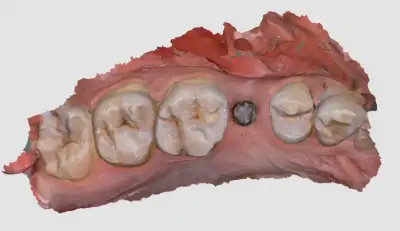

Digital scan image

Day-2

- PMMA crown of proper contour and shade is fixed

- Advised patient to start eating food on that side.

- Patient was asked to report after 3 months for permanent zirconia crown.

PMMA crown